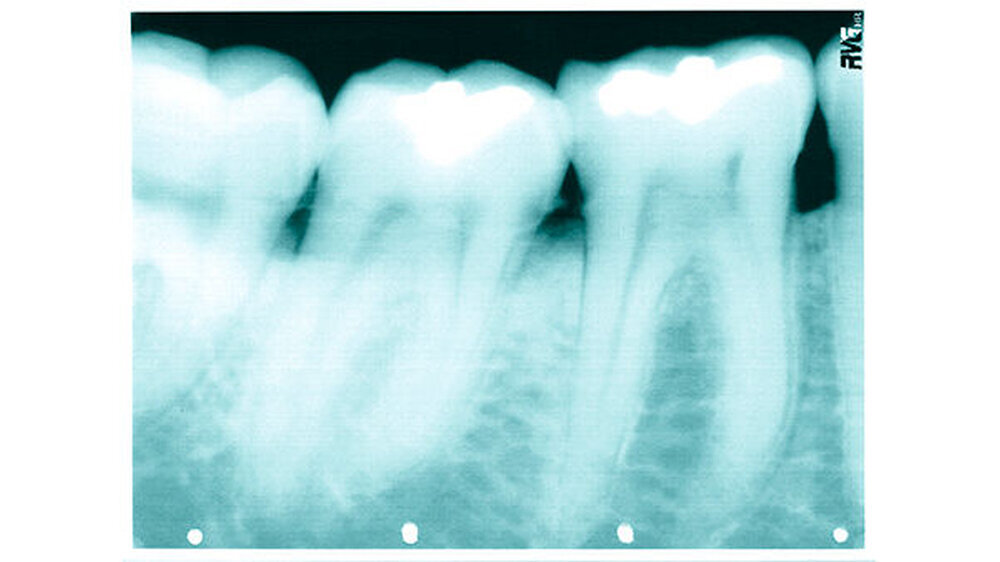

Am 14. März 2003 wurde in der Waal, bei der Gemeine Tiel (Niederlande) ein toter Mann gefunden. Er scheint aus Deutschland zu kommen. Allem Anschein nach lag die Leiche zwischen zwei bis vier Wochen im Wasser.

Das Alter des Toten wird zwischen 30 und 50 Jahren geschätzt. Er hatte schwarze Haare und trug einen Schnurrbart. Seine Größe betrug etwa 175 Zentimeter. Er trug blaue Adidas Sportschuhe in Größe 42, eine blaue Jeans der Marke EDWIN, Größe W31-L32 und dazu einen schwarzen Pullover mit Rollkragen. An seinem rechten kleinen Finger hatte er einen goldenen Trauring. Der Mann war beschnitten.